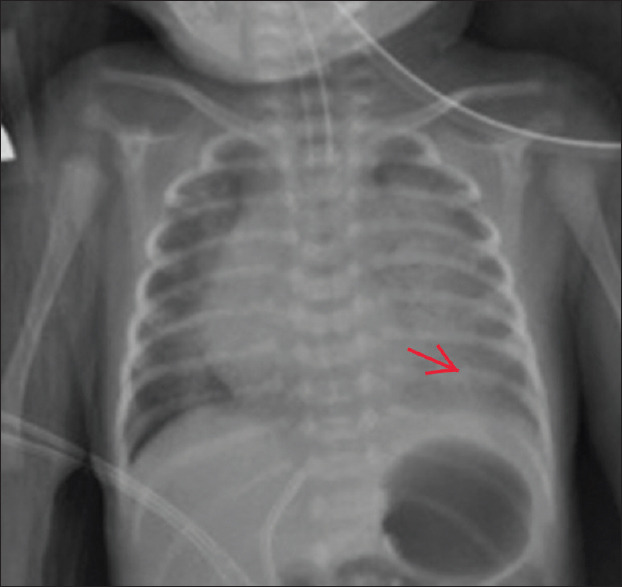

Congenital pulmonary airway malformation (CPAM) together with oesophageal atresia and tracheoesophageal fistula (TOF) is a very rare condition in neonates. We presented a case of an infant with Gross type C oesophageal atresia with TOF coexisting with Stocker Type III CPAM in our centre. It is interesting to know that TOF associated with type III CPAM has never been reported in the literature. The child was delivered through caesarean section, and because of respiratory distress post-delivery, endotracheal intubation was carried out immediately. CPAM was diagnosed by a suspicious finding from the initial chest X-ray and the diagnosis was confirmed through computed tomography scan of the chest. The patient was initially stabilised in a neonatal intensive care unit (NICU), and after the successful ligation of fistula and surgical repair of TOF, lung recruitment was started by high flow oscillatory ventilation. The patient recovered well without complications and able to maintain good saturation without oxygen support through the stay in the neonatal unit. Early recognition of this rare association is essential for immediate transfer to NICU, the intervention of any early life-threatening complications, and for vigilant monitoring in the postoperative period.